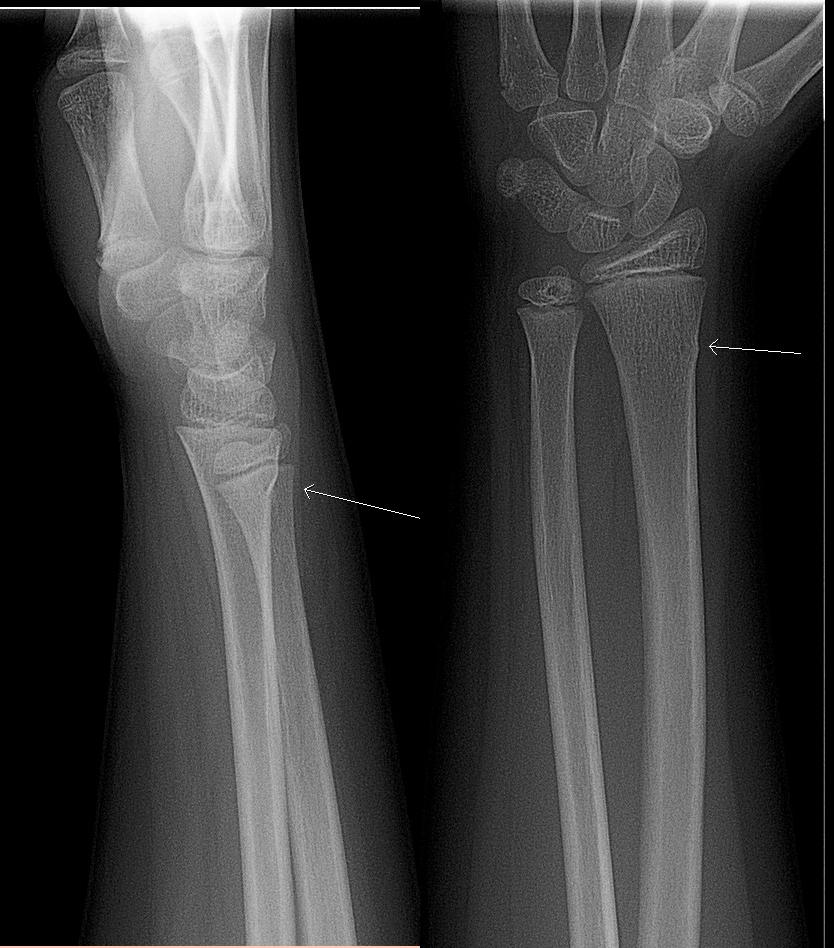

Often a child's forearm bone doesn't break fully but just gets distorted at the surface. This is called a 'greenstick' fracture and doesn't need an operation: it heals in a plaster cast. This X-ray shows a greenstick fracture at the white arrow: just a small bulge of the edge of the bone, rather than a break all the way across:

Greenstick fracture

© Lucien Monfils, CC BY-SA 3.0, via Wikimedia Commons